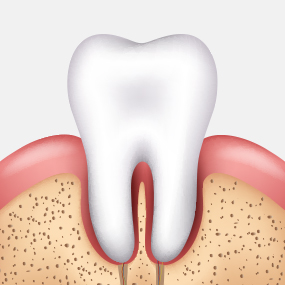

충치가 어느 정도 진행되었는지에 따라 치료 방법은 크게 달라질 수 있습니다. 서울하나치과는 정밀 진단을 통해 치아를 최대한 보존할 수 있는 치료법을 안내해드립니다.

CARIES TREATMENT

치아 겉면인

법랑질의 충치로

통증이 거의 없습니다.